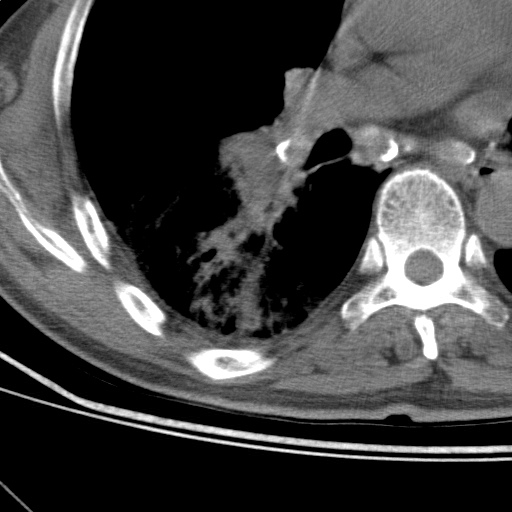

以下是引用随光逐影在2009-5-1 13:53:00的发言:[br]考虑为:1)两肺血行播散型肺结核;2)右肺下叶炎症感染。3)右侧胸膜增厚。